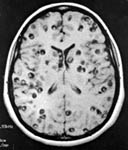

Sau khi thăm khám và điều tra bệnh sử, chụp cắt lớp vi tính có hoặc không có bơm thuốc cản quang đường tĩnh mạch là bước đầu tiên trong chẩn đoán các ca bệnh nghi ngờ ATSL thần kinh. CT não có hoặc không có thuốc cản quan sẽ cho thấy hình ảnh các tổn thương điển hình của ATSL đường kính nhỏ hơn 20mm và không có hình ảnh phản đứng giữa (no midline shift) là hình ảnh gợi ý cao cho thể ATTSL thần kinh (neurocysticercosis). Phần scolex, hoặc phần giác hút của ấu trùng cũng có thể nhìn thấy; đây là đặc trưng bệnh của ATSL thể thần kinh.

Hình 2. trên hình ảnh CT có nang của ATTSL thể thần kinh trong nhu mo não đặc | Hình 3. hình ảnh cộng hưởng từ cho thấy các nang của ATSL thể thần kinh trong nhu mô |

Số lượng, kích thước và vị trí có nang xuất hiện cũng như giai đoạn chu kỳ của nang sán, có thể xác định và có thể tác động đến việc quyết định điều trị. Các nang là các hình ảnh tổng thương dạng điểm có thể phát triển và tồn tại được, nang không bị thoái hóa. Các tổn thương dạng nang chỉ ra biến tính hoặc thoái hóa có một vài phản ứng viêm bao quanh. Cuối cùng, các nang hình thành calci hóa là một bằng chứng các nang đã tồn tại lâu có thể đã chết. Chăm sóc phải được tiến hành khi có thể còn nghĩ đến nhiều nguyên nhân khác (lao, bệnh ký sinh trùng khác, di căn từ nơi khác đến, hoặc ung thư nguyên phát của não hoặc hình ảnh abces não) khi một tổn thương tìm thấy trên phim chụp cắt lớp.

Hình ảnh trên phim chụp cộng hưởng từ cũng là công cụ hữu ích để chẩn đoán ATSL thể thần kinh và có thể tốt hơn cả chụp cắt lớp CT để phát hiện các thương tổn trong não tủy, trong cuống não, trong não thất. Việc áp dụng nó nên cân nhắc khi CT không chẩn đoán ra. CT và siêu âm là rất nhạy để phát hiện các tổn thương ATSL tại mắt và hệ cơ xương.